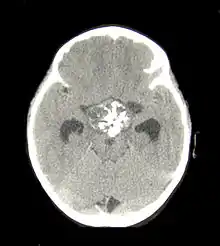

In some cases, a powerful 3T (Tesla) MRI scanner can help define the location of critical brain structures affected by the tumor. The histologic pattern consists of nesting of squamous epithelium bordered by radially arranged cells. It is frequently accompanied by calcium deposition and may have a microscopic papillary architecture. A computed tomography (CT) scan is also a good diagnostic tool, as it detects calcification in the tumor.[13]

In the adamantinomatous type, calcifications are visible on neuroimaging and are helpful in diagnosis.

CT scan showing a craniopharyngioma